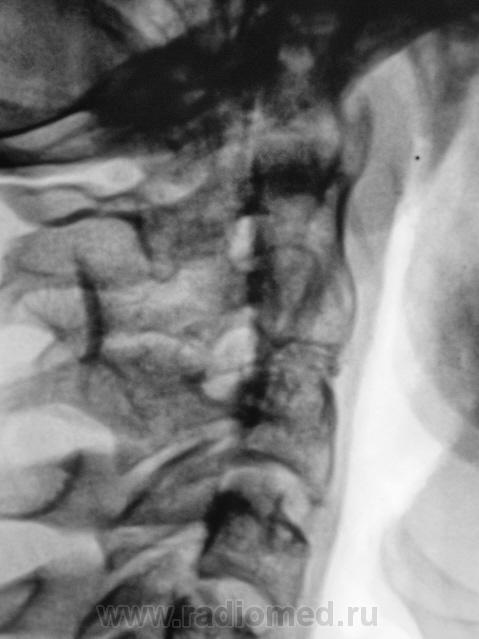

Подросток направлен в рентгеновский кабинет с диагнозом "сколиоз"...

Сколиоз-то сколиоз, но генеза "аномального".

Это синостоз тел верхних шейных позвонков и С6-С7? И боковые клиновидные полупозвонки в верхнегрудном отделе? Это синдром Клиппеля-Файля? А может и Шпренгеля...